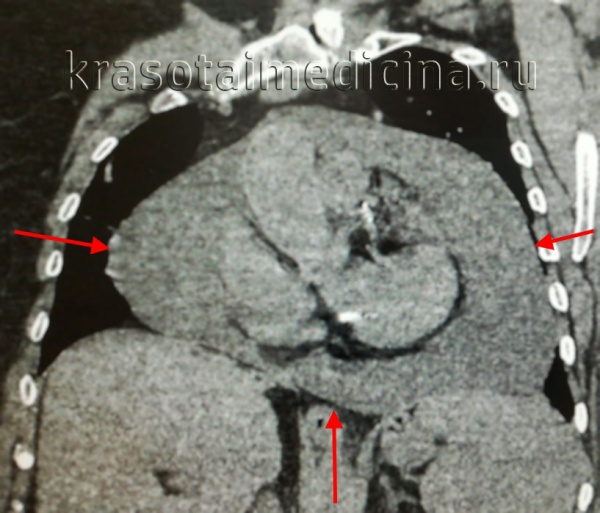

- Рентгенография грудной клетки. На рентгенограмме при значительном объеме жидкости наблюдается увеличение тени и сглаживание сердечного контура, изменение формы сердца (треугольная – при длительно существующем хроническом экссудате), ослабление пульсации сердца. Мультиспиральная КТ подтверждает наличие патологического выпота и утолщение перикардиальных листков.

- Лучевая диагностика. Рентгенография легких информативна для диагностики экссудативного перикардита (наблюдается увеличение размера и изменение силуэта сердца: шаровидная тень – характерна для острого процесса, треугольная – для хронического). При накоплении в полости перикарда до 250 мл экссудата размеры тени сердца не изменяются. Отмечается ослабленная пульсация контура тени сердца. Тень сердца плохо различима за тенью наполненного экссудатом перикардиального мешка. При констриктивном перикардите видны нечеткие контуры сердца из-за плевроперикардиальных сращений. Большое количество спаек может обусловить "неподвижное" сердце, не изменяющее форму и положение при дыхании и смене положения тела. При «панцирном» сердце отмечаются известковые отложения в перикарде. КТ грудной клетки, МРТ и МСКТ сердца диагностирует утолщения и кальцификацию перикарда.